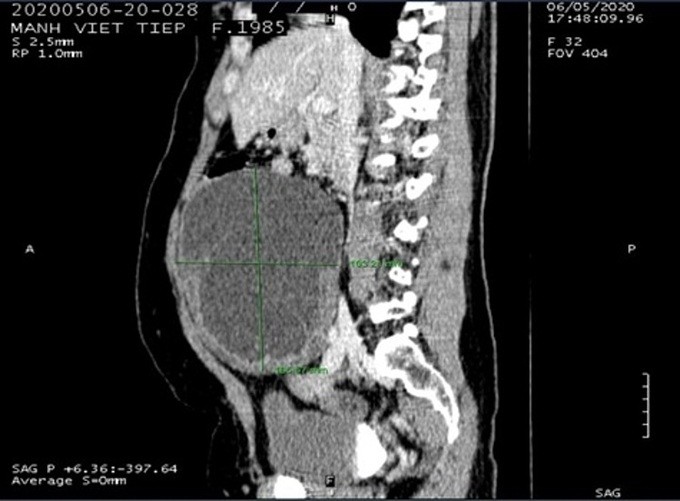

Khối u buồng trứng chiếm hết ổ bụng

Kết quả chụp chiếu ghi nhận bệnh nhân có khối u to 17 cm chiếm hết ở bụng, bác sĩ Khoa Phụ sản chẩn đoán u nang buồng trứng trái xoắn, chỉ định phẫu thuật cấp cứu.

Khi mổ, các bác sĩ phát hiện khối u nang buồng trứng trái bị xoắn vặn một vòng, vòi trứng và các tổ chức buồng trứng tím đen do máu tụ nên không thể bảo tồn. Kíp phẫu thuật tiến hành gỡ xoắn, cắt bỏ toàn bộ khối u cho bệnh nhân.